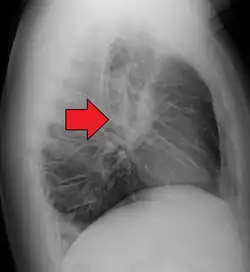

Hilar adenopathy especially on the person's left (AP CXR) -

Hilar adenopathy especially on the person's left (lateral CXR) -